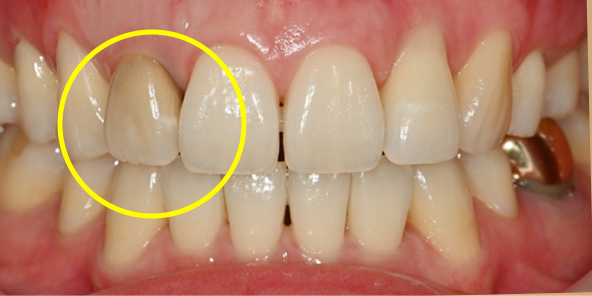

Final Implant Results

BEFORE/AFTER

BEFORE

AFTER